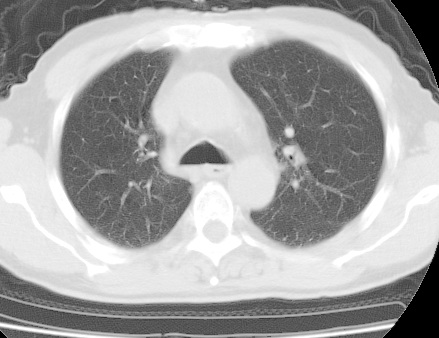

考虑右肺中叶不张,请大家发表意见

右肺中叶不张,中叶支气管开口不清,建议支气管镜检查。

中叶肺不张是没问题的,但为什么不在肺门区加薄扫呢?要查原因。

右肺中叶支气管闭塞,中叶肺不张,右侧肺门见肿块影。中心型肺癌的可能大。建议支气管镜检查。

右中叶体积明显缩小,且其支气管未显示,先考虑:中心型肺癌班右中叶肺不张。

建议:支气管镜检查。

(有病变的地方应该薄层扫描,方便于诊断)

右肺中叶支气管狭窄,中叶不张,建议纤支镜检